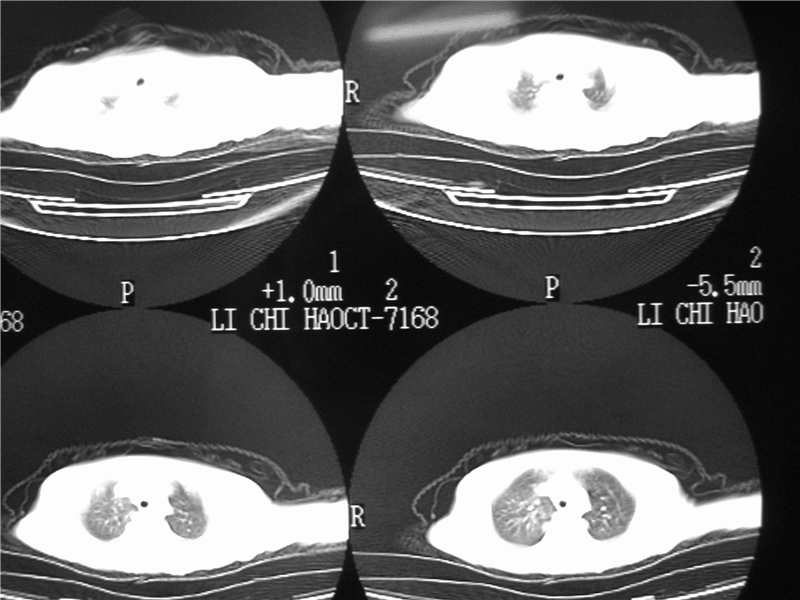

标题: PED3236:男2岁进食花生米后发烧10天。

右肺中叶及下叶内段大片实变密度增高影,可见支气管气象,肺炎.

摄吸气及呼气相对比片,本例为有肺中叶阻塞性炎症、不张,右肺下叶阻塞性炎症。

1)右肺炎症并右肺中叶肺不张,右肺上叶充气不良。2)右侧支气管异物不排除。

结合病史,考虑气管异物所致。

再有,我们16排ct有气管重建功能,肯异物效果可以。

结合临床考虑支气管异物并阻塞性肺炎、肺不张。